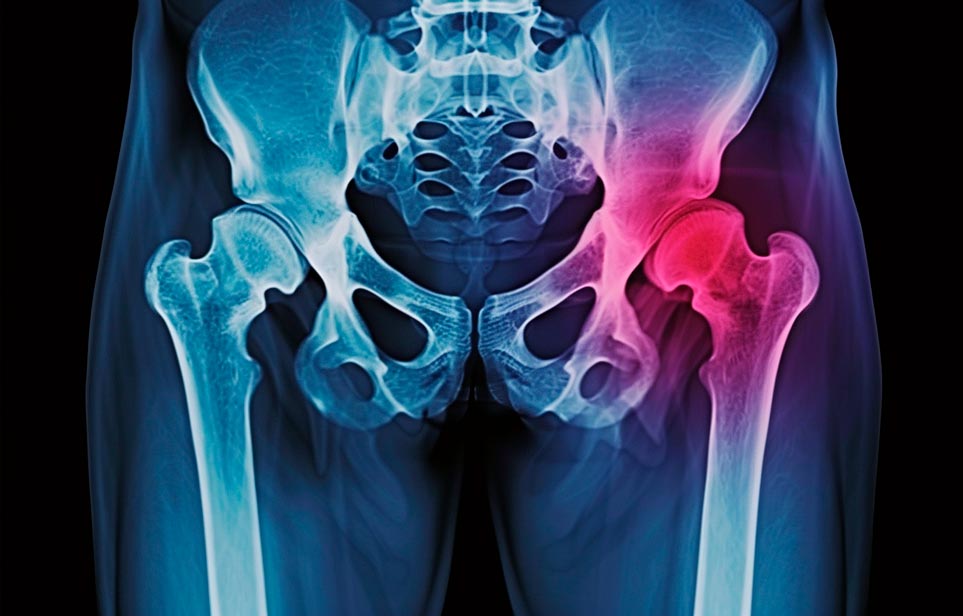

Эффективная и профессиональная реабилитация после перелома шейки бедра в Туле осуществляется по демократичным ценам лучшими специалистами современной медицинской клиники «Заботливые люди» с применением персонального подхода к каждому пожилому человеку с такой тяжёлой травмой бедренной кости ноги. В процессе осуществления такой специализированной услуги все наши пациенты имеют возможность получения качественного и достойного обслуживания, эффективного восстановления. Лучший дом престарелых позаботиться о Вашем близком человеке.

Такая травма в большей части случаев возникает у граждан преклонного возраста. При её появлении на протяжении длительного времени сохраняются болевые и неприятные ощущения в области паха, при которых серьёзно ухудшается качество жизни, возникает множество последствий для его жизни и здоровья.

По какой симптоматике можно определить перелом шейки бедра?

Выявить его можно по возникновению следующей тревожной симптоматики:

- Визуально повреждённая нога сокращается на несколько сантиметром из-за сокращения мышц.

- Стопа выворачивается наружу.

- В лежачем положении человек не может поднять ногу.

При такой симптоматике важно незамедлительно обращаться к специалистам для получения всей необходимой помощи, терапии и восстановления после перелома шейки бедра. Если не оказать помощи старику, то это приведёт к гноению, инвалидности, иным видам осложнений.